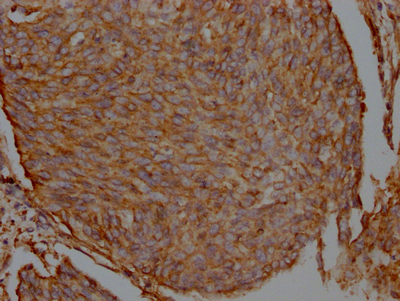

IHC image of CSB-RA548809A0HU diluted at 1:100 and staining in paraffin-embedded human cervical cancer performed on a Leica BondTM system. After dewaxing and hydration, antigen retrieval was mediated by high pressure in a citrate buffer (pH 6.0). Section was blocked with 10% normal goat serum 30min at RT. Then primary antibody (1% BSA) was incubated at 4℃ overnight. The primary is detected by a Goat anti-rabbit IgG polymer labeled by HRP and visualized using 0.05% DAB.